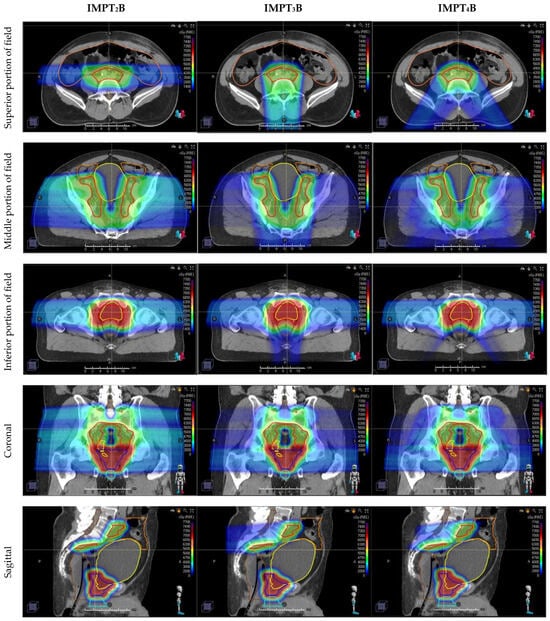

| IMPT2B | two-field IMPT beam arrangement using opposed laterals |

| IMPT3B | three-field IMPT beam arrangement using opposed laterals inferiorly matched to a Posterior–anterior beam superiorly |

| IMPT4B | four-field IMPT beam arrangement using opposed laterals inferiorly matched to 2 Posterior oblique beams superiorly |